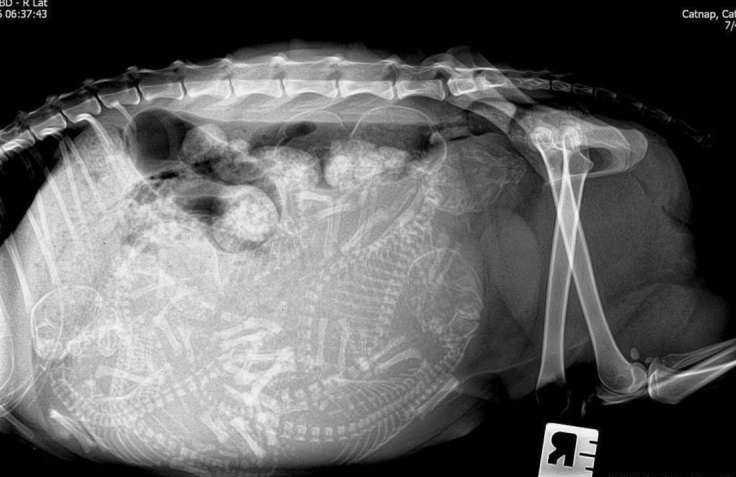

▼怀孕的猫咪